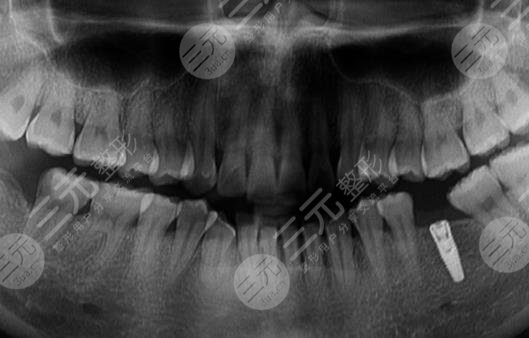

手术项目:种植牙

我是一个程序员,每天都会熬夜工作,身体的机能大量的下降,其实牙齿也并不是特别的好看,以前长过尽头牙,但是在专业医生的指导下已经将牙齿拔除了,但现在的门牙也不是特别的美观,较为的丑陋,还有一点脱落的现象,吃东西也较为的不方便。为了让自己能够吃想吃的东西,也为了让自己的口腔状态变得更加的精美一点点,去到了专业的整形医院进行了诊断,然后牙科的专业医生说可以做种植牙治疗,来使整个口腔变得更加的美观。

经过一系列的医学检测和诊断之后,较终确定了手术的方案就是种植牙治疗,做完手术之后,迫不及待的去镜子面前看了看自己的口腔状态,也用手机的相机照了照自己的牙齿,发现种植牙和自己原本的牙齿形态较为的合适,看不出有任何的区别,根本就没有突兀的感觉,果较为的自然和和谐。